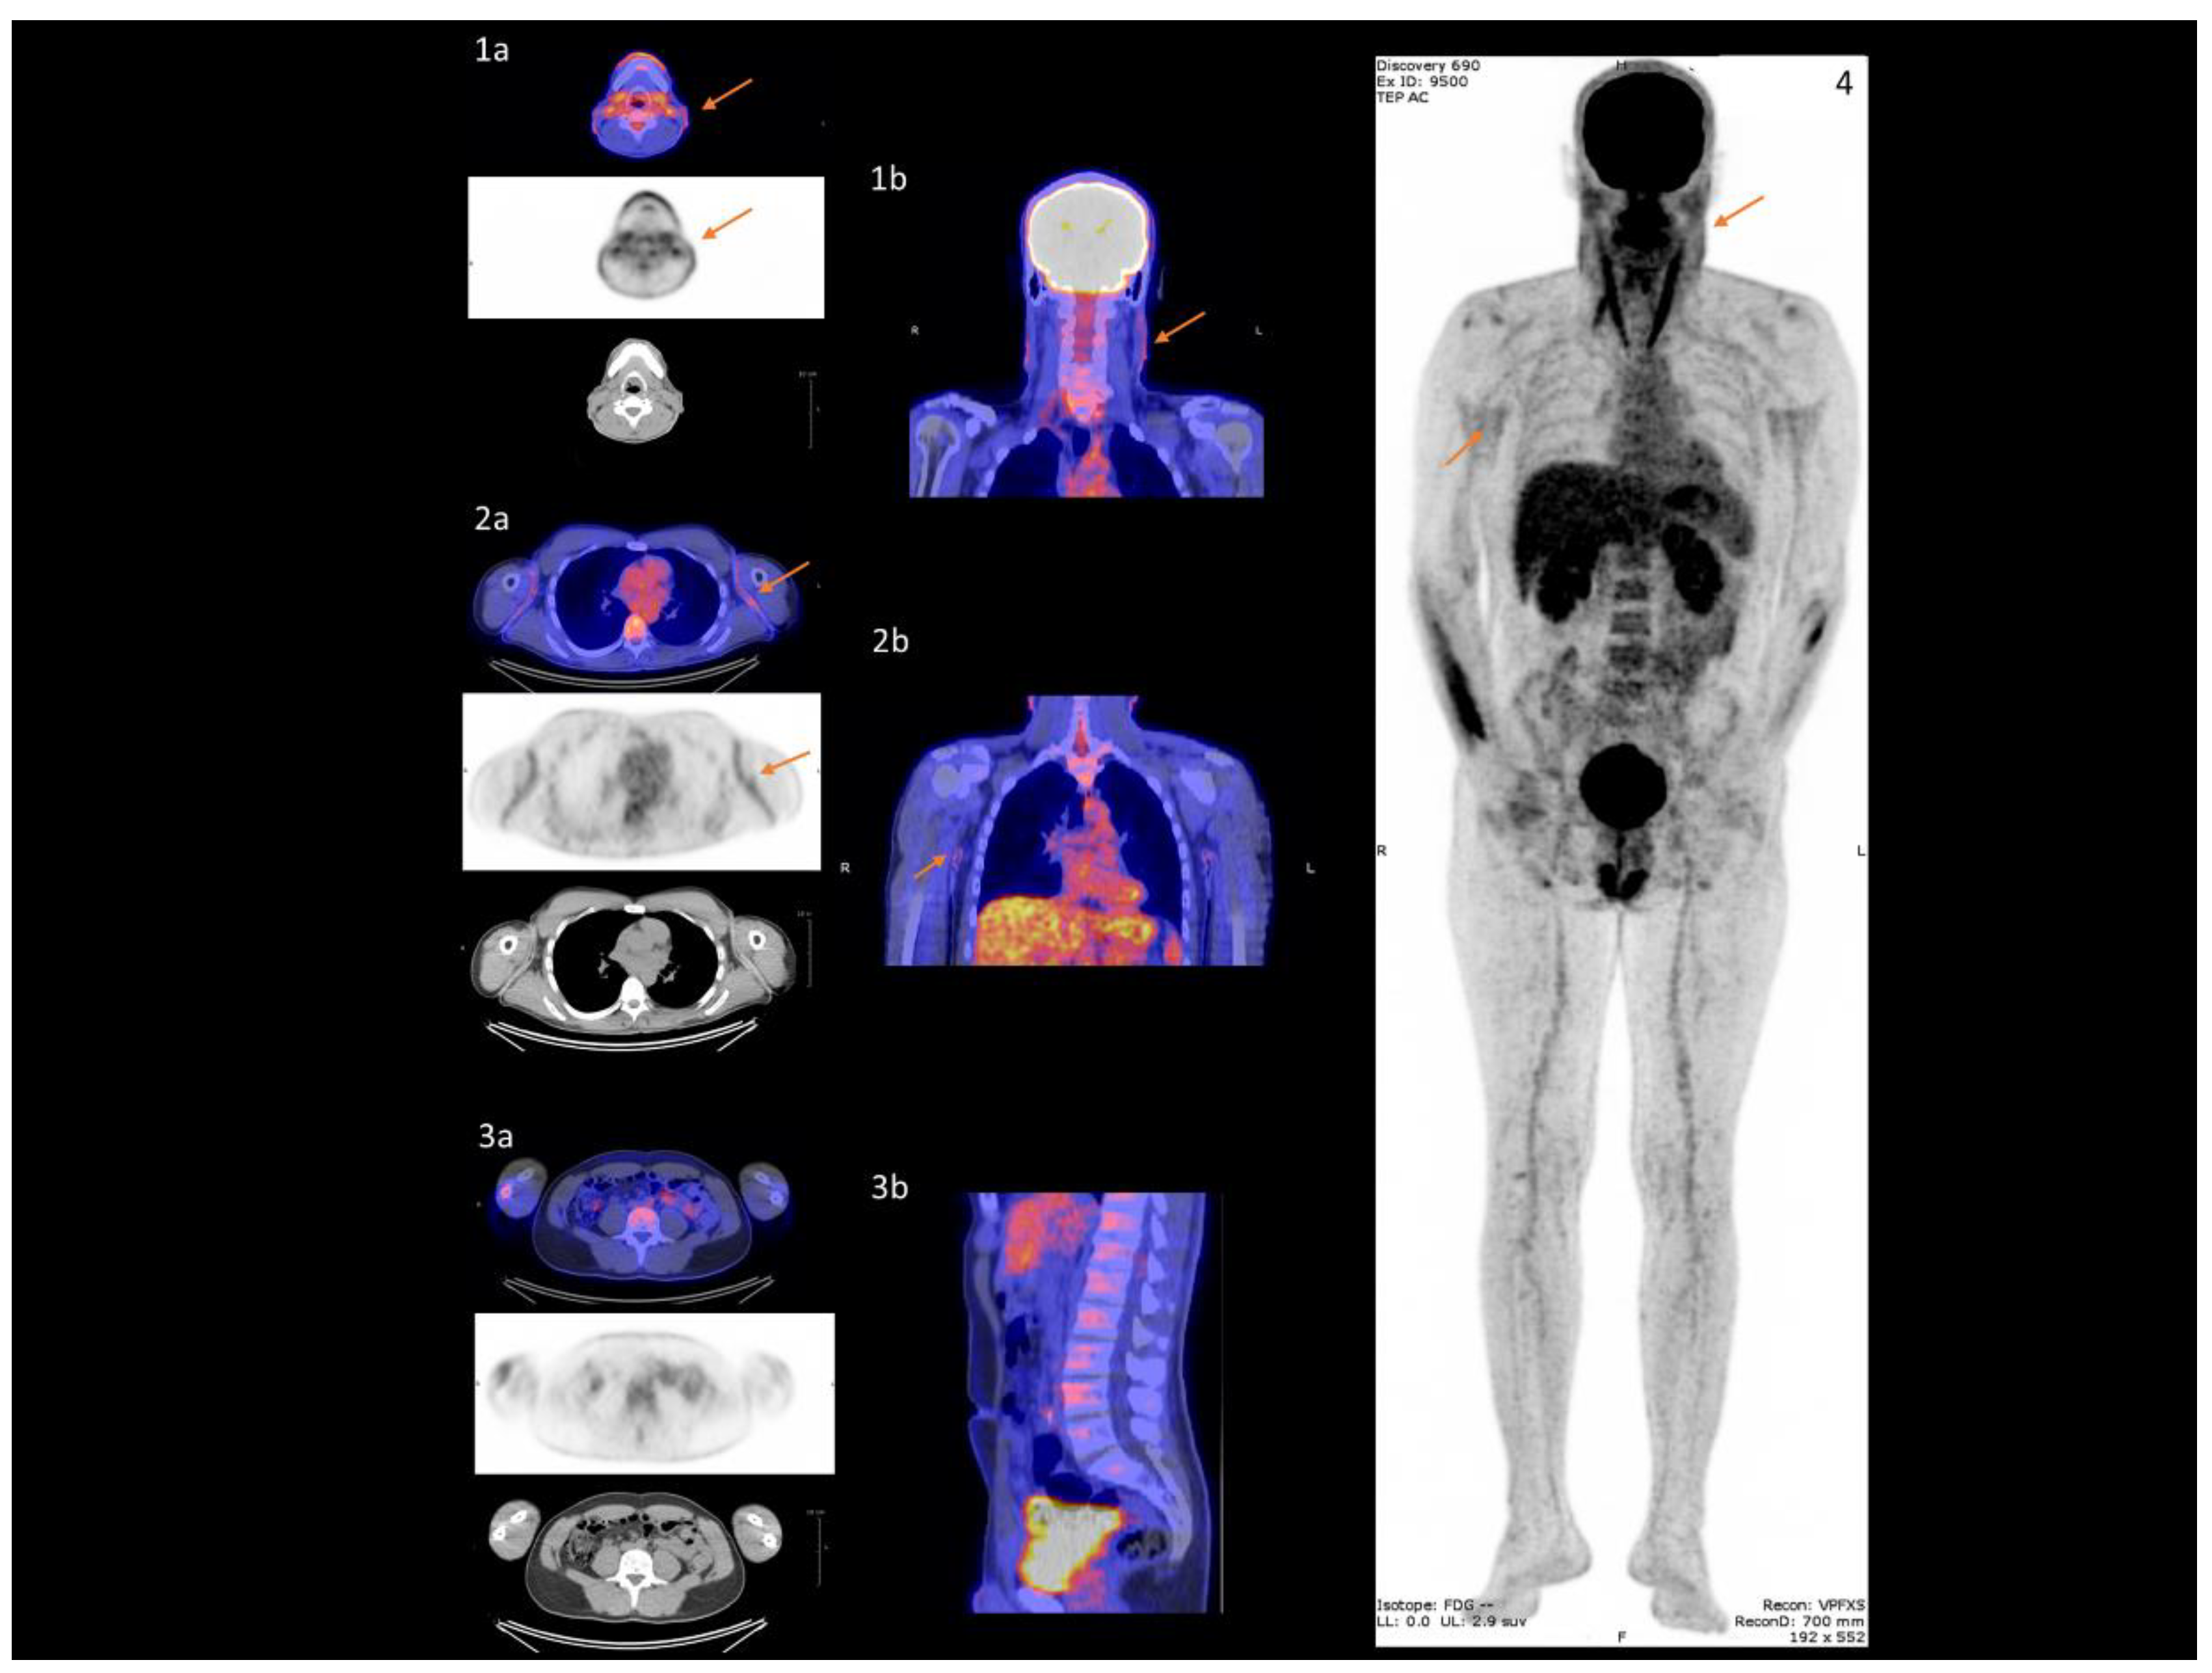

- Mention, P.; Lacoeuille, F.; Leftheriotis, G.; Martin, L.; Omarjee, L. 18F-flurodeoxyglucose and 18F-sodium fluoride positron emission tomography/computed tomography imaging of arterial and cutaneous alterations in pseudoxanthoma elasticum. Circ. Cardiovasc. Imaging 2018, 11, e007060. [Google Scholar] [CrossRef]